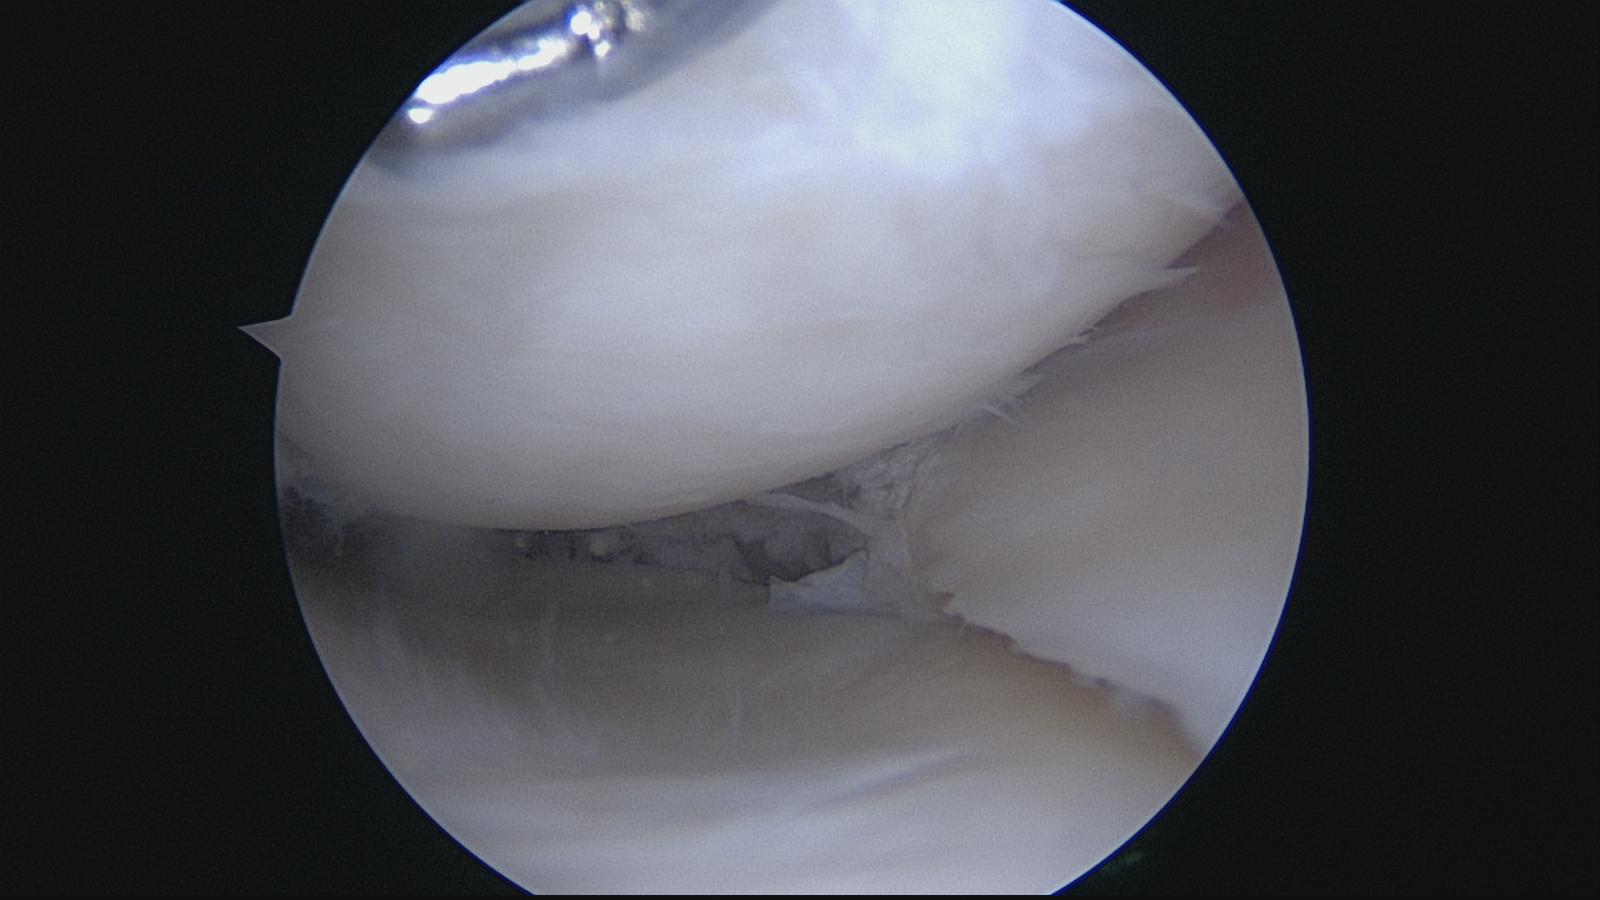

К слову оборудование (современное ) дорогое , артроскопическая стойка в "полном фарше" стоит под 8 млн. руб.. фото сделано через камеру артроскопа. Латеральный отдел сустава ( посередине мениск, сверху бедренная кость снизу большеберцовая)

так выглядит лоскутный разрыв миниска до .

А На этой фоте запущенный сустава внагружаемой зоне мыщелков хрящ разволокнен или отсутствует, дегенеративные изменения миниска хряща и застрелил разрыв миниска .